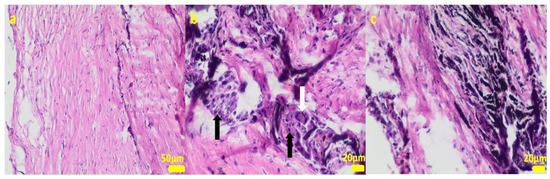

2.2. In Vivo Study

4.3. Cell Cultures